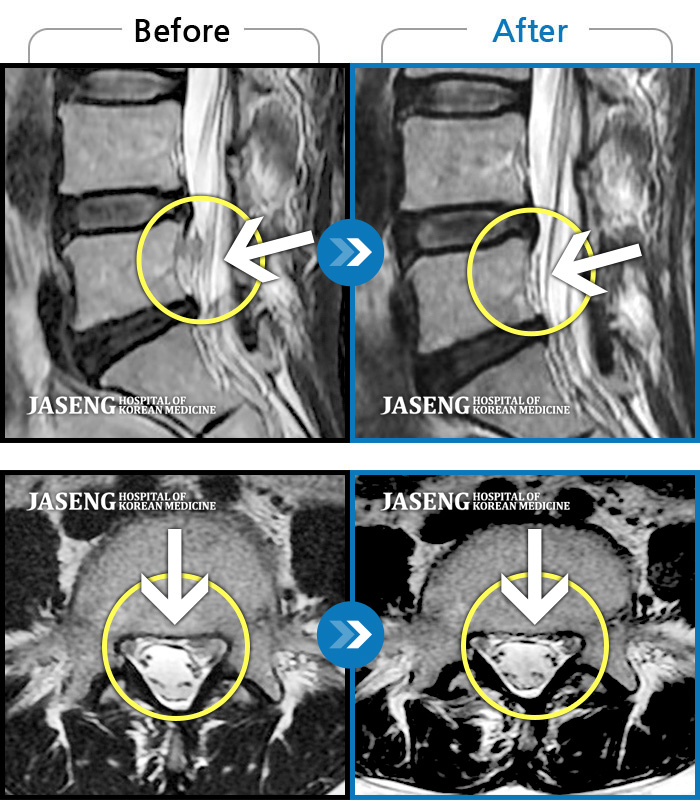

MRI 치료사례

푸쉬업을 여러 번 반복한 뒤 극심한 하요부 통증 및 우측 하지부 저림